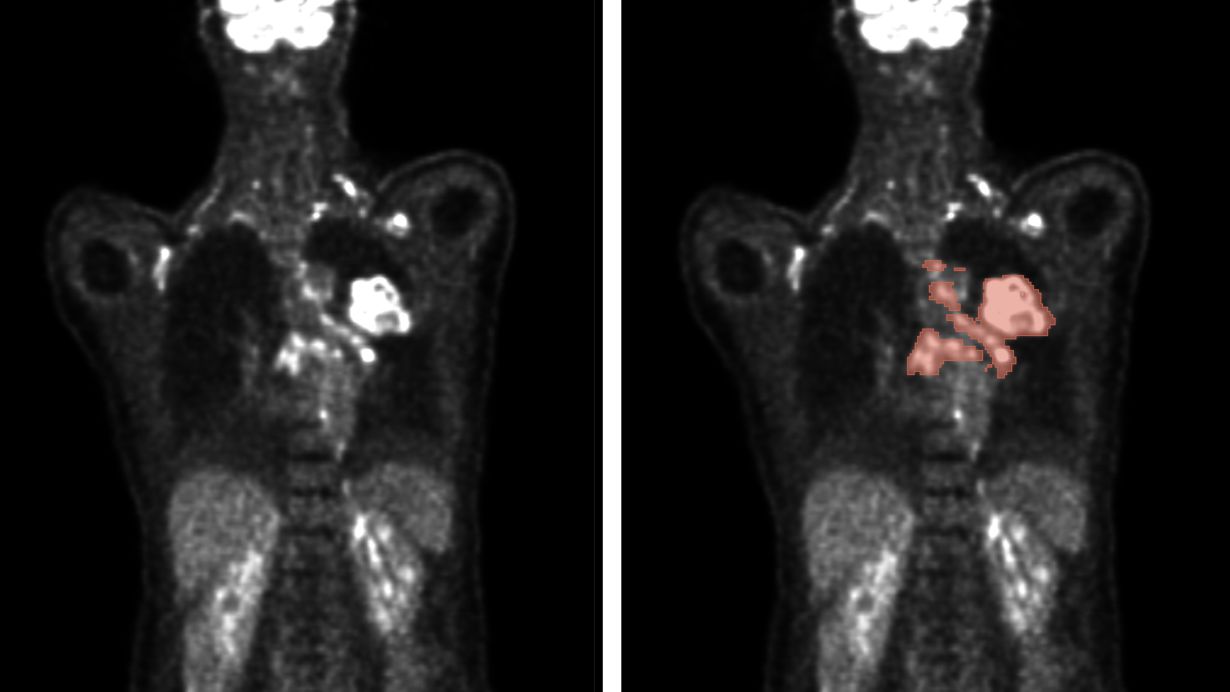

🔬 El Instituto de Tecnología de Karlsruhe (KIT) ha logrado un avance significativo en el uso de la inteligencia artificial para mejorar el análisis de imágenes médicas. En el marco del concurso internacional autoPET, los investigadores del KIT alcanzaron el quinto lugar entre 27 equipos globales. Este concurso se centra en la segmentación automática de lesiones tumorales en imágenes de PET/CT, utilizando algoritmos de aprendizaje profundo. Estos algoritmos permiten una detección más precisa y eficiente de la ubicación y tamaño de los tumores, lo cual es crucial para el diagnóstico y tratamiento del cáncer. La investigación, publicada en la revista Nature Machine Intelligence, destaca que un conjunto de algoritmos es más efectivo que los individuales para identificar lesiones tumorales. Sin embargo, se requiere más investigación para mejorar la robustez de estos algoritmos y su aplicación en entornos clínicos.